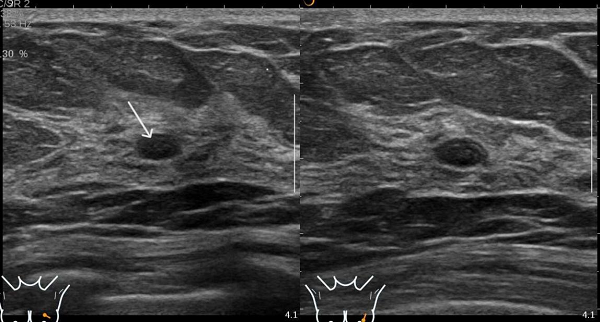

患者B钼靶检出多发钙化灶,超声虽未显示钙化,但发现了钼靶未显示的实性结节(如图3、4)。

图4 患者B的超声图像,显示未见钼靶所示钙化灶,但扫查到乳腺实性低回声结节(图中箭头处)